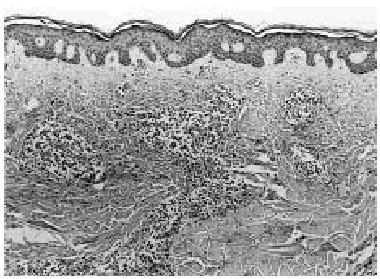

Se realizó una biopsia de la lesión cutánea (fig. 2), que demostró una infiltración perivascular superficial y profunda y perianexial por grupos de células grandes con gran desproporción núcleo-citoplasmática, citoplasma amplio eosinofílico y núcleo irregular con nucléolo prominente (fig. 3), siendo sugestiva de infiltración por LMA.

Fig. 2.--Imagen panorámica en la que se observa en la dermis reticular una infiltración multinodular por células leucémicas.

Histopatológicamente7, 11, 12 muestran un denso infiltrado granulocítico dérmico de intensidad variable, de distribución difusa o nodular, preferentemente perivascular y perianexial, que ocasionalmente invade el tejido celular subcutáneo. El infiltrado característicamente respeta la parte alta de la dermis papilar. Las células neoplásicas son de gran tamaño, con citoplasma abundante y núcleo oval o indentado, que contiene uno o varios nucléolos. En el caso de la LMA M29, que es la que presenta nuestro paciente, predominan las células mononucleares de mediano o gran tamaño, con citoplasmas escasos y núcleos basófilos excéntricos con nucléolos evidentes (mielocitos y mieloblastos atípicos). Las técnicas de inmunohistoquímica pueden ser utilizadas para confirmar la naturaleza del infiltrado leucémico13. La mayoría de las células leucémicas de la LMA tiñen fuertemente su citoplasma con lisozima y CD43. Las células neoplásicas bien diferenciadas son positivas con cloroacetato esterasa y alfa-1 antitripsina7.